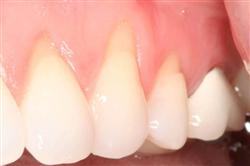

Normally gum tissue surrounds and protects the delicate roots of your teeth. Exposed tooth roots are prone to tooth decay, root canals, discoloration and actual jawbone loss. All of this can lead to tooth loss in advanced cases.

Functional Soft Tissue Grafting replaces the missing gum tissue and protects your teeth. For this reason, soft tissue grafting may be recommended even for back teeth.